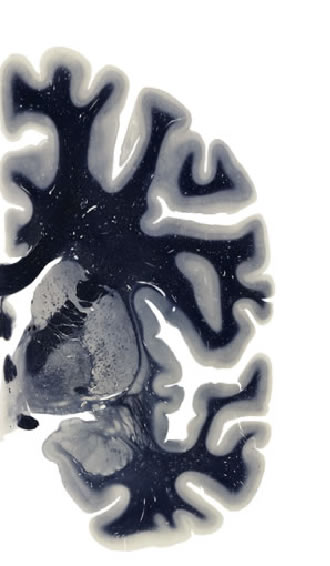

Hi-Resolution Sections · Cells (Nissl Staining) · Virtual Microscopy

Frontal sections (Nissl) from the Atlas Brain:

Macroscopy

Slice ID:

r3-1307

Plate NR:

ca 24

Position:

2,5 mm